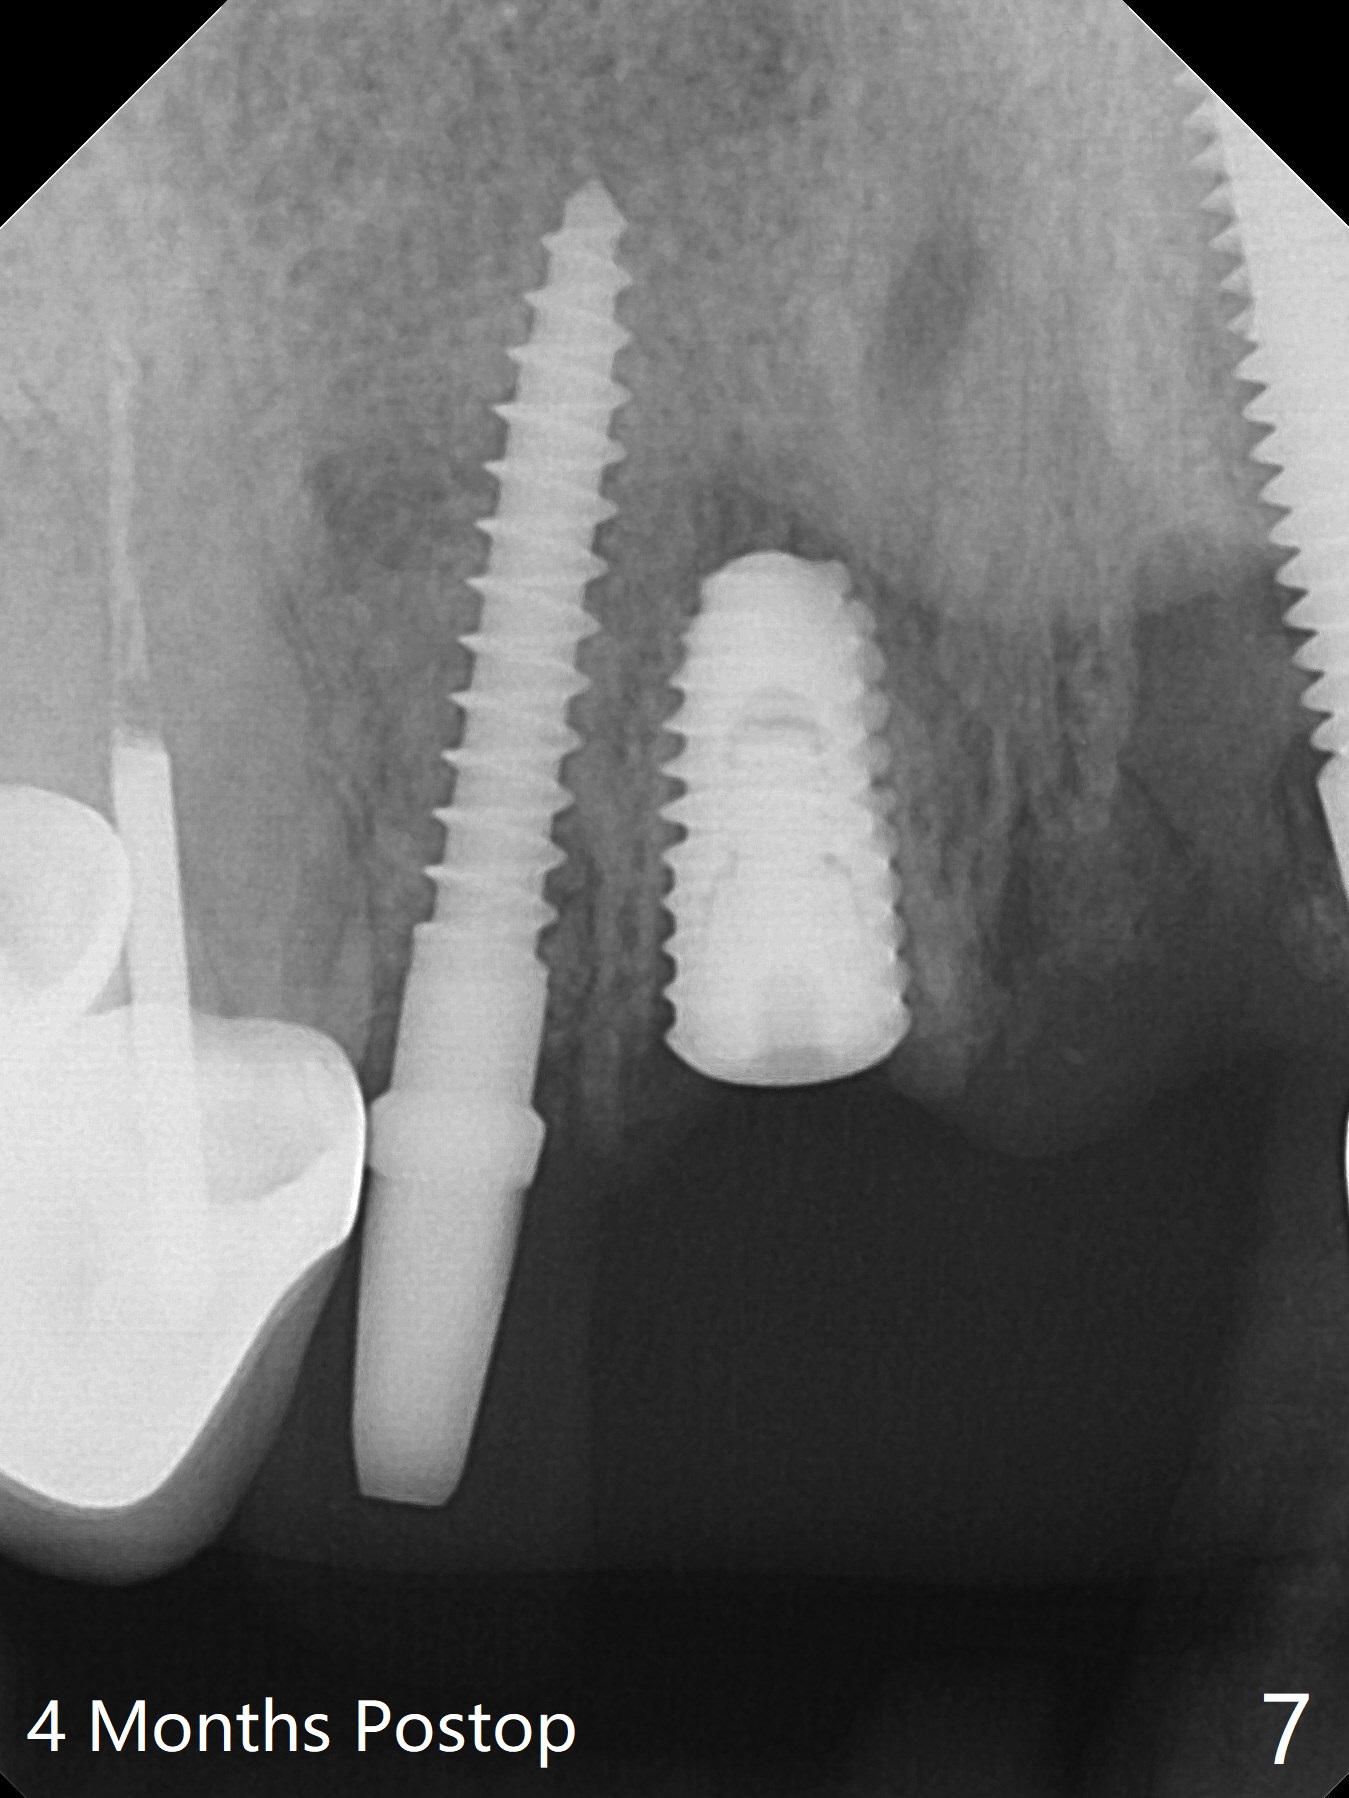

Socket Shield in Narrow Space

The edentulous area at #7 is narrow both buccopalatally and mesiodistally, whereas the crowns of the neighboring teeth are long (Fig.1,2). For the latter reason, it is difficult to remove the apical portion of the root, including gutta percha with surgical handpiece (Fig.3 *) for socket shield (Fig.2 *). To avoid the perspective implant touching socket shield, initial osteotomy is palatal. When a 2 mm drill is being used, the coronal end of the palatal plate starts to perforate. A 2.5x14 mm 1-piece implant is placed with 30 Ncm (Fig.4). The palatal plate is thin (Fig.5). Preop CT will help determine the position of initial osteotomy. The buccal gingiva seems to have been re-attached to the underlying alveolus and the provisional 1 month postop (Fig.6). The teeth #8 and 9 fracture (an implant is placed at #8 and bone graft at #9, while the implant at #7 is osteointegrating (Fig.7). In fact the shield is exposed without symptom. A year postop, another dental provider sends a photo of apparently hemorrhagic gingiva around #7 crown (Fig.8). A few days later with oral hygiene instruction, the gingiva around the exposed root piece is healthy (Fig.9). The root surface is reduced; with socket shield, there is no buccal plate collapse; in contrast the neighboring buccal plate (at #8 and 9) is concave (Fig.10). There is minimal exposure 11 days postop (Fig.11). The gingiva palatal to the shield is erythematous, a possible sign of periimplantitis. The socket shield at #7 appears to be fused with the buccal plate 11 months postop (Fig.12), as compared to the implant at #10 nearly 4 years postop (Fig.14). The buccopalatal widths at #7 and 10 are equivalent (Fig.13,15).